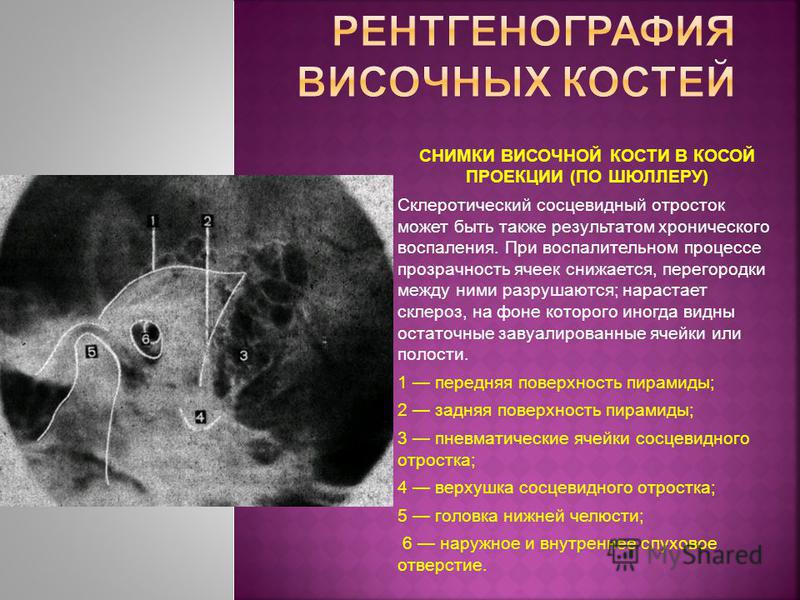

Анатомия сосцевидного отростка